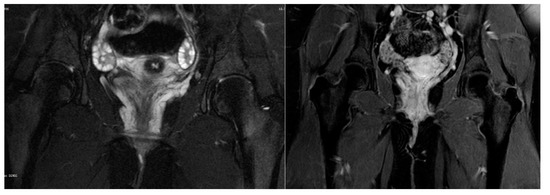

Ultrasound evaluation of the vulvar masses revealed a helical, retractable, tubular structure with dense fluid content of low flow, which varied in size with pressure and had a morphology of nervous, varicose dysplasia. Varicography and ascending venography were performed by femoral approach to assess communications between varicosities and deep pelvic veins. No areas of arteriovenous dysplasia or reflux were observed on the tributaries of either the ovarian or the internal iliac veins. The examination was completed by catheterization of the vulvar mass on the right side. The vascular lake was delineated in the area of the right labium minus, which drained through estuarine tributaries into the iliac vein. The aforementioned findings were confirmed by magnetic resonance angiography (MRA), as shown in Figure 2. Vulvar varices of maximal diameter of 3 mm were reported, which were drained into dilated pelvic floor tributaries of the internal iliac vein. Connections with the long saphenous veins were also apparent through the superficial external pudendal vein; however, incompetence or dilatations were not noted. However, the supine position of the adolescent during the examination might have underestimated the degree of the disorder.

Figure 2. Magnetic resonance angiography: Vulvar varices draining into dilated pelvic floor tributaries of internal iliac vein.